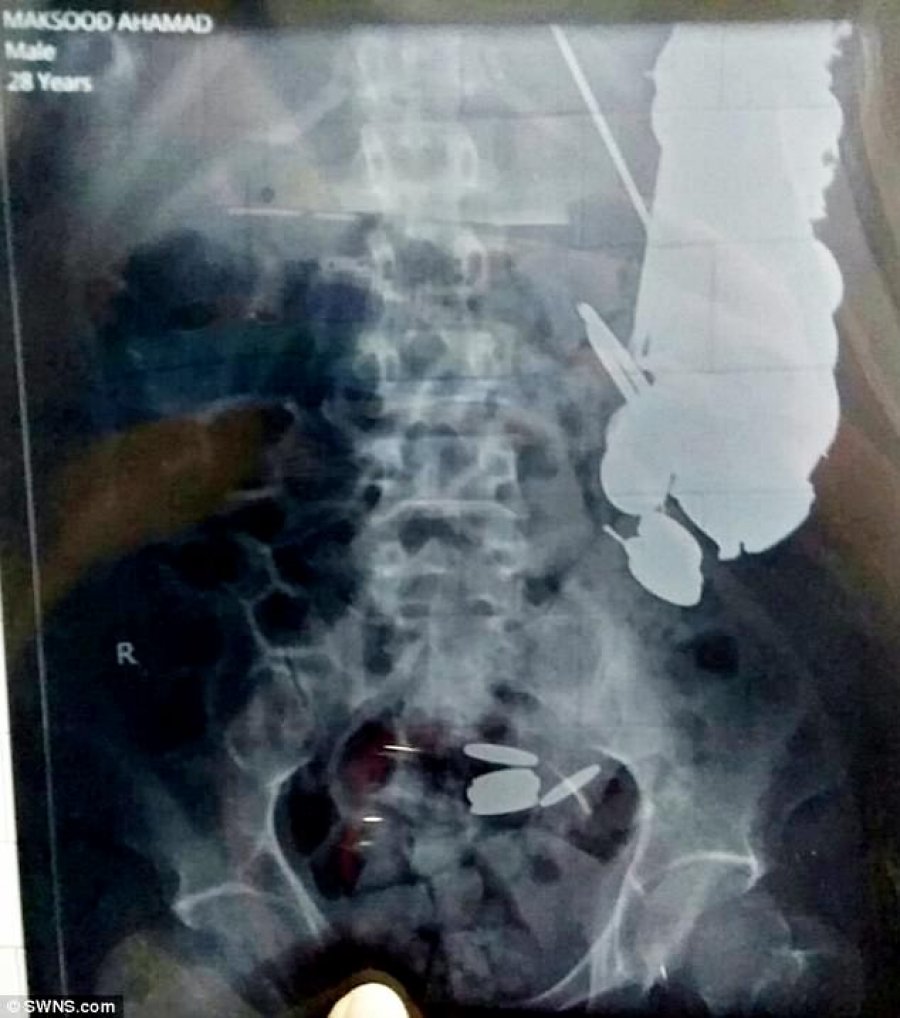

Maksud Khan, 35 vjeç, u dërgua në një spital në Madhya Pradesh të Indisë me dhimbje barku, por doktorët i gjetën në stomak 263 monedha dhe rreth 100 gozhda dhjetëra brisqe dhe sende të tjera.

Kirurgët nuk humbën kohë dhe reaguan menjëherë duke realizuar ndërhyrjen kirurgjikale duke hequr 7 kilogramë lëndë të huaj nga stomaku i pacientit.“Pacienti ka paqëndrueshmëri mendore.

Askush tjetër nuk do ta bënte një gjë të tillë. Ai punonte me një triçikël që transportonte mallra dhe shpesh gëlltiste monedha që i jepeshin nga klientët e tij”, thanë mjekët, përcjell tch.

Ndërkohë, të afërmit thanë se ai kishte rënë në depresion.Mjekët u shprehën se operacioni është kryer në momentin e duhur pasi gozhdët kishin shkaktuar gjakderdhje dhe po ja vinin jetën seriozisht në rrezik 35-vjeçarit, i cili tashmë është jashtë rrezikut për jetën, përgatiti Koha. (b.an)